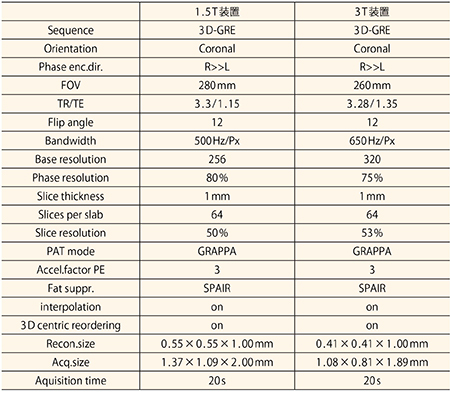

RVS用MRIは,脂肪抑制併用3D-GREシーケンス(日立:TIGRE)を用いる。造影剤自動注入器を用い,呼吸停止下で撮像を行う。RVS用MRIは,腹臥位MRIとは別日に撮像している。当院での腹臥位乳房MRIとRVS用MRIの撮像法を表1に示す。

表1 当院における腹臥位乳房MRIとRVS用MRIの撮像法

当院のRVS用MRIの撮像条件を表2に示す。呼吸停止時間は,1.5T,3T共に20秒である。RVSを行う際には,RVS用MRIの全シリーズ,全スライスを超音波診断装置に読み込むことができる。RVSでは4相のシリーズを切り替えて表示することが可能である。MPR画像を示す(図4)。

表2 当院のRVS用MRIの撮像条件